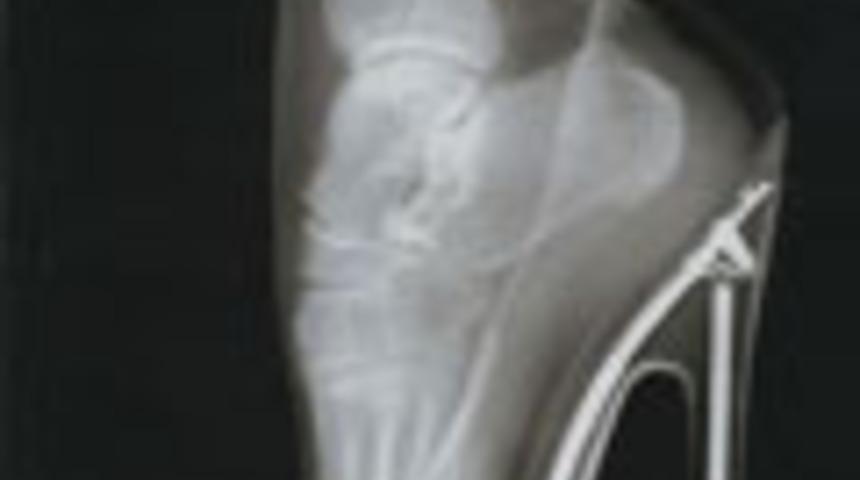

Ayak bileği incinmeleri

Yüksek topuklu ayakkabı giyenlerde vücudun ağırlık merkezi öne kayar ve insan parmak ucunda yürüyormuş gibi olur. Ağırlığı destekleme alanı daraldığı için de dengenin çabuk bozulması sonucu düşme, ayak burkulması ve ayak bileğinde incinmeler meydana gelebilir.